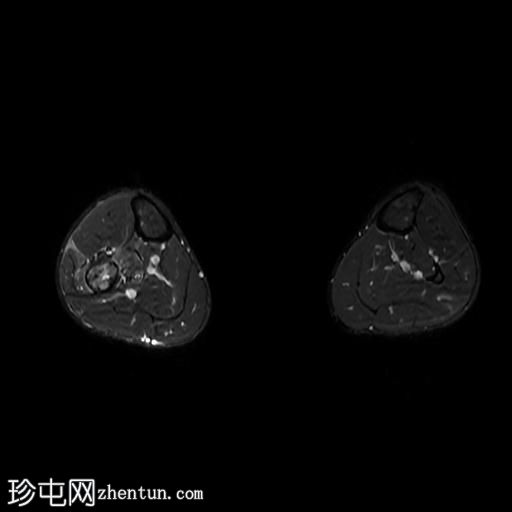

冠状位

T2加权像

腓骨可见广泛的骨髓水肿,伴有明显的皮质和骨膜增厚,整个腓骨均呈高信号。腓骨外侧中下三分之一交界处可见局灶性皮质破坏,并可见一条高信号瘘管延伸至周围皮肤。

此外,软组织(包括肌肉和皮下组织)也受累。

腓骨弥漫性骨髓信号异常,伴有明显的皮质和骨膜增厚,窦道自腓骨延伸至皮下区域。MRI 影像学表现符合腓骨骨髓炎。